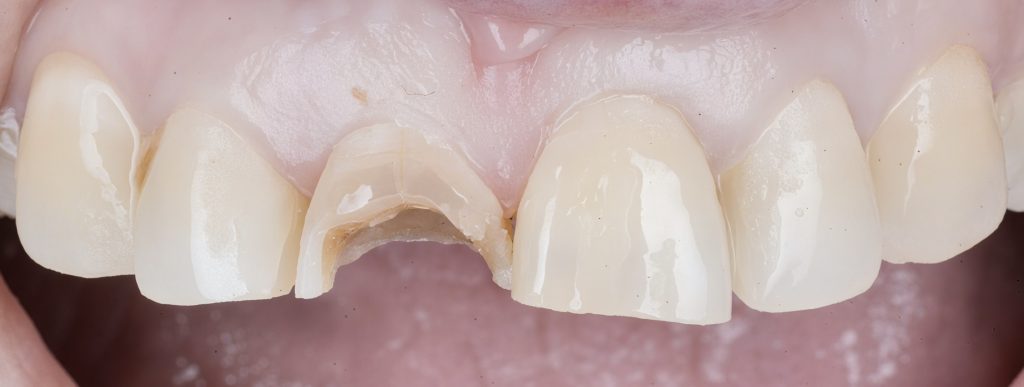

1 Pre-operative Assessment

Clinical exam revealed a coronal fracture exposing previous access and visible sealer remnant. Periapical radiograph confirmed a metallic fragment lodged in the apical third with a faint radiolucency (Fig 1–2).